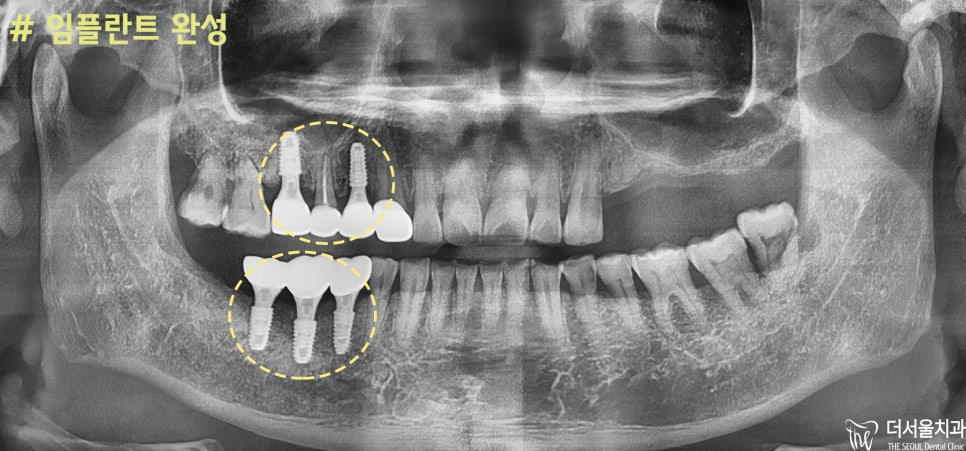

완성된 모습을 보여드리겠습니다.

주변 부위와 평행하게

픽스쳐가 잘 심긴 것을 확인할 수 있습니다.

기성 지대주가 아닌

잇몸 맞춤형 지대주로 제작해서

환자에게 딱 맞는 보철을 붙여드릴 수 있었습니다.